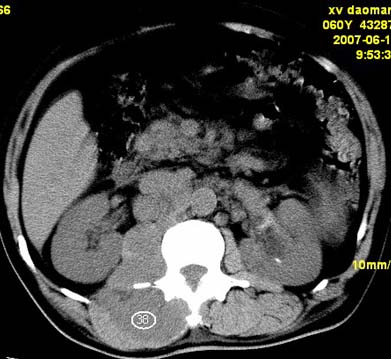

以下是引用还珠格格在2007-6-26 15:05:00的发言:[br]右侧腰大肌、同侧竖脊肌明显肿胀,呈不均匀密度减低影,右肾受压右上前移,脂肪间隙部分消失,另左侧肾盂内可见高密度影,是结石还是造影剂? 不知道病人用造影剂没有?考虑 右侧腰大肌及右侧竖脊肌寒性脓肿形成。[br][br][本贴已被 还珠格格 于 2007-6-26 15:21:35 修改过]

以下是引用小初学者在2007-6-26 15:42:00的发言:[br]1\\右侧腰大肌、同侧竖脊肌脓肿[br]2\\左侧肾盂结石

以下是引用刘明在2007-6-26 16:00:00的发言:[br][br]右侧竖直肌及腰大肌肿胀,脂肪间隙难辨,腹膜后血管旁见多个肿大淋巴结影,椎体附件右侧有压迫吸收、未见硬化迹象,考虑椎旁冷脓肿可能[br]左侧肾盂内可见高密度影,周围有毛刺,本图象是平扫,不是增强,应该是结石[br]